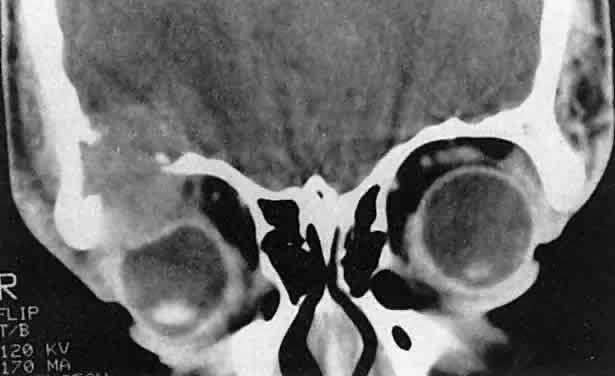

Orbital myositis may represent a greater proportion of cases of IIPT in childhood than in adulthood, and involvement of multiple extraocular muscles may occur more frequently in children than inadults. In orbital myositis, early diplopia and increased discomfort with attempted eye movement are typical symptoms. CT may show enlargement of one or more extraocular muscles in one or both orbits (Figs. 21 and 22). When a single muscle is involved, the specter of a primary or metastatic neoplasm within the muscle may be raised. However, external inflammatory signs, considerable pain and limited motility, and an explosive onset of symptoms within 24 hours all suggest orbital myositis. The uniform enlargement of the muscle, including its tendinous insertion (see Fig. 22), also helps distinguish the process from a neoplasm, which might be expected to produce a more focal, globular expansion. Echography may support the diagnosis of inflammation by showing edema in the episcleral space as a relative sonolucency between the scleral and orbital fat echoes (Fig. 23). Its CT counterpart is an increase in the radiodensity and thickness of the ocular tunica.

Fig. 21. A. This 16-year-old boy had acute onset of bilateral proptosis, pain, diplopia, chemosis, and conjunctival injection. B. Bilateral enlargement of the superior and medial rectus and inferior oblique muscles. Other sections showed similar involvement of other extraocular muscles.

Fig. 22. The uniform enlargement of the left medial rectus muscle, including its tendinous insertion, is characteristic of orbital myositis.

Fig. 23. Acoustic discontinuity between the globe and the orbital fat indicates inflammatory edema in Tenon's space.

In dacryoadenitis, external inflammatory signs are localized to the superotemporal quadrant, and CT shows enlargement of the lacrimal gland (Fig. 24). Lacrimal gland inflammation may be bacterial, viral, or a variant of IIPT. It is possible, however, that many cases of “idiopathic” dacryoadenitis represent unidentified viral infections. In bacterial dacryoadenitis, a leukocytosis with a left shift may be present.96 In questionable cases, a 1-week course of oral antibiotics can be administered to these patients. Among children, the probability that an enlarged lacrimal gland represents neoplasia rather than inflammation is lower than among adults, although epithelial lacrimal gland tumors occasionally may occur in the pediatric population and can produce external inflammatory signs. If the general signs and symptoms of IIPT are lacking, a biopsy should be performed.

Fig. 24. A. Nonbacterial dacryoadenitis may be unilateral or bilateral. External inflammatory signs are maximal in the superotemporal quadrant. B. The left lacrimal gland is enlarged, with a shape molded by the globe and orbital walls. A neoplasm usually can be ruled out by analysis of the history, CT findings, and echographic characteristics, but a biopsy may be required in equivocal cases.